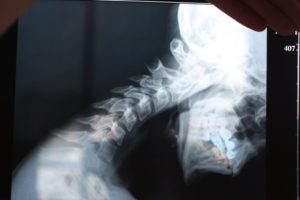

- Снимок рентгена. Многих волнует вопрос о том, показывает ли обычный рентген клиническую картину сотрясения полностью, выявляет ли такой метод определенные нарушения, возникшие в результате получения травмы и многие другие характеристики. Рентгеновский снимок необходим для изучения возможных структурных изменений костей черепа.

- Если результаты показали наличие микротрещин, осколков костной ткани или больших трещин, то медики диагностируют тяжелый или средний вид травмы. Недостатком этого способа является его малоинформативность, сосуды, окружающие ткани мозга, остаются неисследованными. Чтобы картина болезни была полной, нужно применить более точные методы диагностики.